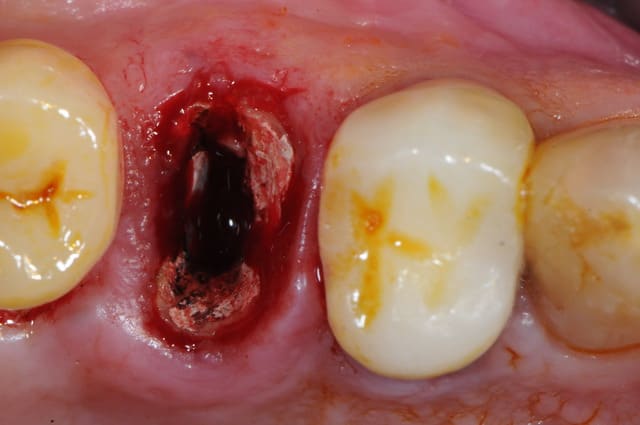

-fracture 25

-infection

-extraction (oups la ccm sur implant s'est descellée...)

-pas de pose d'implant car destruction de la paroi vestibulaire sur près de 5 mm

-pas de lambeau mais décollement vestibulaire muco-périosté à travers l'alvéole d'extraction et interposition d'une membrane de Collagen AT entre l'os et le périoste

-comblement BioOs et recouvrement avec même type de membrane

-conjonctif pédiculé tracté (comme j'ai pu) pour fermeture du site d'"extraction.